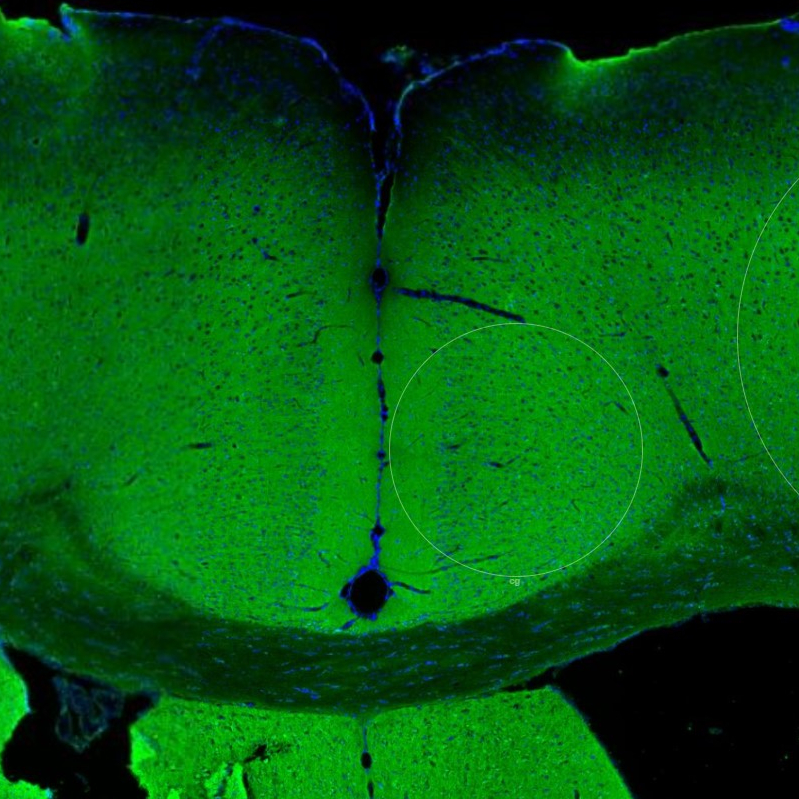

Immunohistochemistry analysis in human cerebral cortex and pancreas tissues using HPA030900 antibody. Corresponding NCAM2 RNA-seq data are presented for the same tissues.